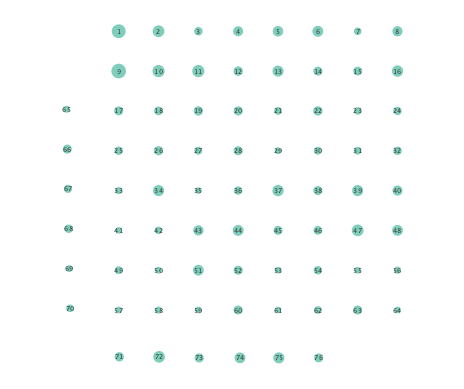

Figure 2 depicts networks inferred from different algorithms for both preictal and ictal intervals of the time series. The figure illustrates results obtained by the linear SVARM, and the K-SVARM approach with and without kernel selection. Each node in the network is representative of an electrode, and it is depicted as a circle, while the node arrangement is forced to remain consistent across the four visual representations. A cursory inspection of the visual maps reveals significant variations in connectivity patterns between ictal and preictal intervals for both models. Specifically, networks inferred via the K-SVARMs, reveal a global decrease in the number of links emanating from each node, while those inferred via the linear model depict increases and decreases in links connected to different nodes. Interestingly, the K-SVARM with kernel selection recovered most of the edges inferred by the linear and the K-SVARM using a polynomial kernel, which implies that both linear and nonlinear interactions may exist in brain networks. Clearly, one is unlikely to gain much insight only by visual inspection of the network topologies. To further analyze differences between inferred networks from both models, and to assess the potential benefits gained by adopting the novel scheme, several network topology metrics are computed and compared in the next subsection.

First, in- and out-degree was computed for nodes in each of the inferred networks. Note that the in-degree of a node counts its number of incoming edges, while the out-degree counts the number of out-going edges. The total degree per node sums the in- and out-degrees, and is indicative of how well-connected a given node is. Figure 3 depicts nodes in the network and their total degrees encoded by the radii of circles associated with the nodes. As expected from the previous subsection, Figures 3 (a) and (b) demonstrate that the linear SVARM yields both increases and deceases in the inferred node degree. On the other hand, the nonlinear SVARM leads to a more spatially consistent observation with most nodes exhibiting a smaller degree after the onset of a seizure (see Figures 3 (c) and (d)), which may imply that causal dependencies thin out between regions of the brain once a seizure starts.